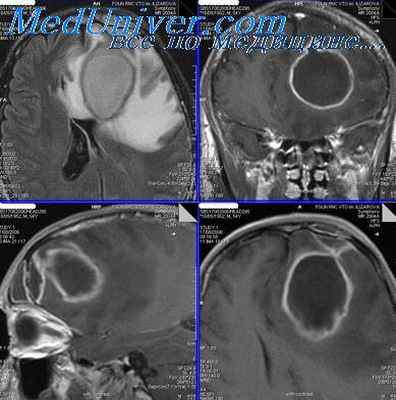

9. Клинический случай

17. Абсцесс лобной доли мозга – образование гнойника в белом веществе лобной доли мозга, которое протекает в 4 стадии;

последовательно развиваются

начальная, латентная, явная и терминальная;

первые две стадии малосимптомны, сопровождаются

симптомами синусита, головной болью, небольшим

повышением температуры тела, слабостью; явная

стадия характеризуется манифестацией всех групп

симптомов

(общемозговых,

менингеальных,

очаговых

и

инфекционно-воспалительных);

терминальная – симптомы дислокации мозга и

центральная

асфиксия

.